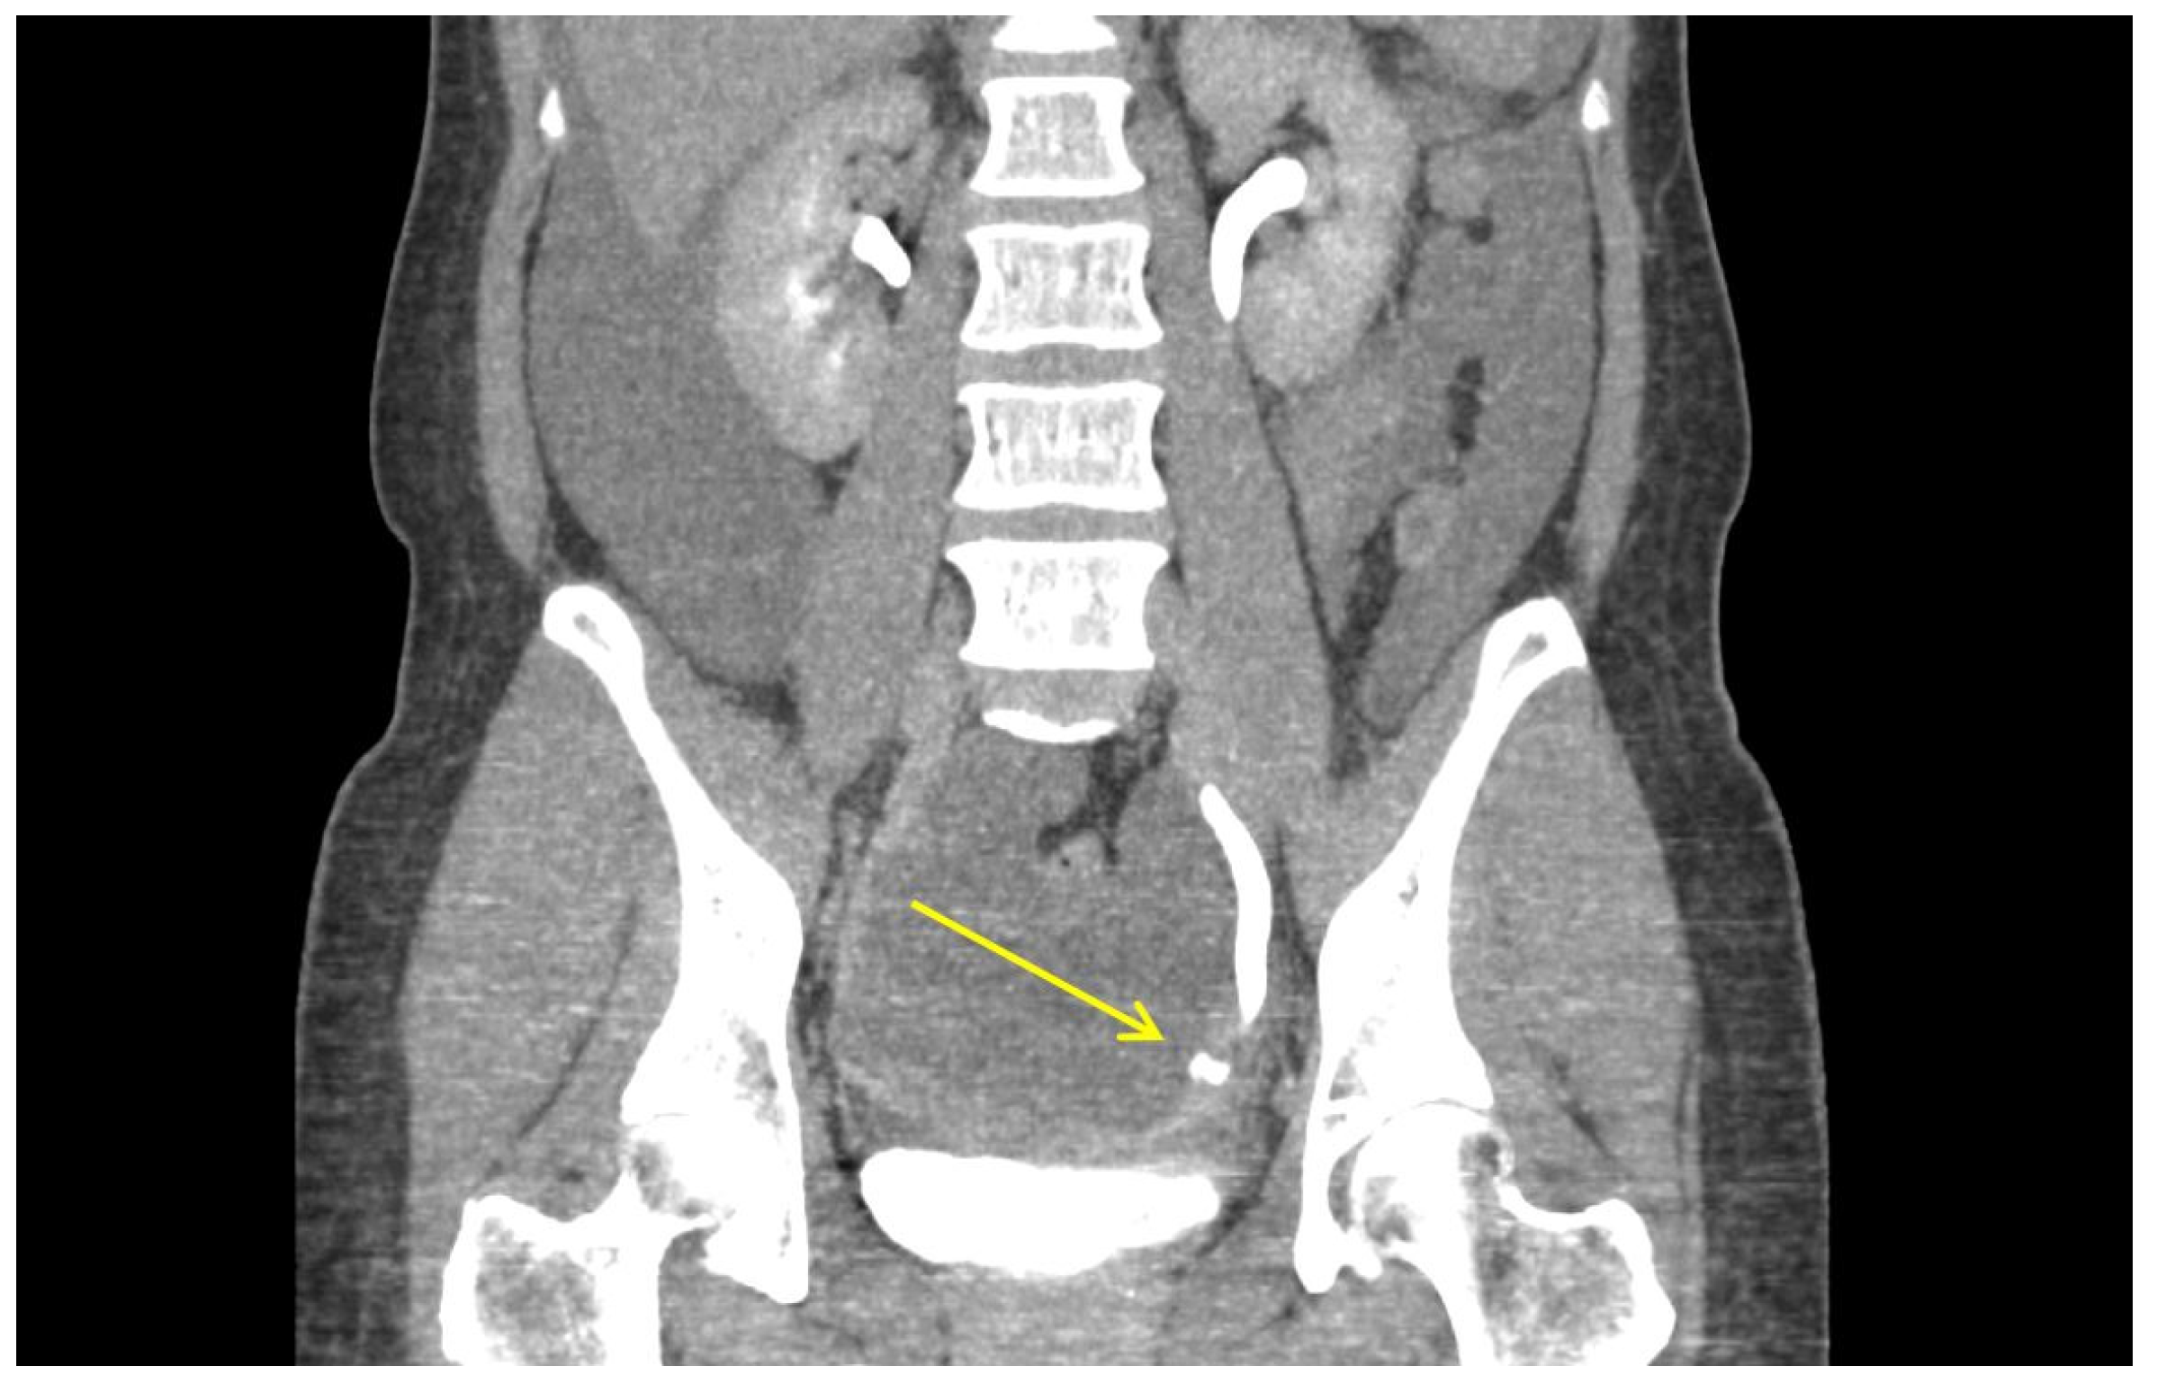

| Post-operative urography CT a findings | Profuse amount of fluid collection in the abdominal cavity. Contrast leakage at left distal ureter during the excretory phase. No hydronephrosis in both ureters. Mild peritoneal thickening, suggestive of peritonitis. Otherwise unremarkable. |